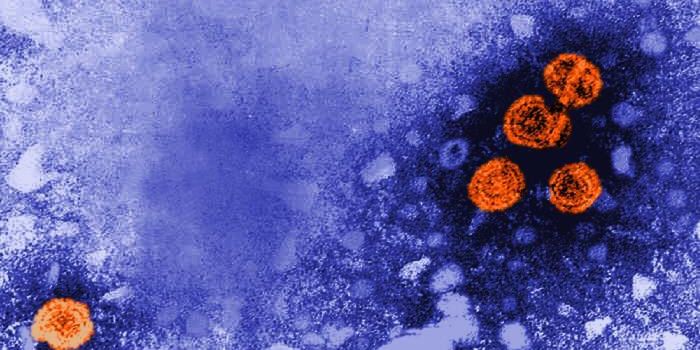

OCT 14, 2021Genetics & GenomicsRespiratory syncytial virus (RSV) are thought to be incredibly common; research has suggested that almost everyone is ev ...